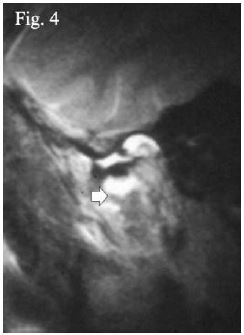

Con respecto a esta última estructura, resulta controversial si se observa o no en RNM. La mayoría de estudios no especifican8,25,32, pocos afirman que no24, otros sólo frente a casos de patologías o distención por efusión23,28,29,33, siendo muy pocos los que afirman que sí puede verse15,17 (figura 3), otros a raíz de casos de fractura como Kim et al.34, sólo mencionan que se observa como una línea oblicua (figura 4), pero pero no especifican dónde se encuentra; Sun y Wan mencionan su ruptura y presentación como una masa expansible al canal auditivo18. Sin embargo, ninguno especifica cómo es que se ve. Sakhavalkar et al.35, en el año 2016 publicaron un estudio evaluando y midiendo el ancho de la cápsula articular, basados en parámetros indirectos, pero tampoco especifican cómo se observa.